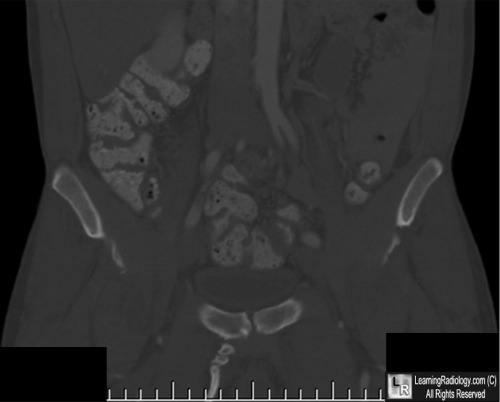

Pelvic Digit. (Above). Frontal and lateral radiographs of the hip demonstrate a well-corticated bony protuberance arising from the region of the right pubic bone with a suggestion of segmentation (yellow and white arrows). (Below) A coronal reformatted CT image of the pelvis confirms the presence of the pelvic digit with pseudo-articulations (white circle).

For these same photos without the arrows, click here and here